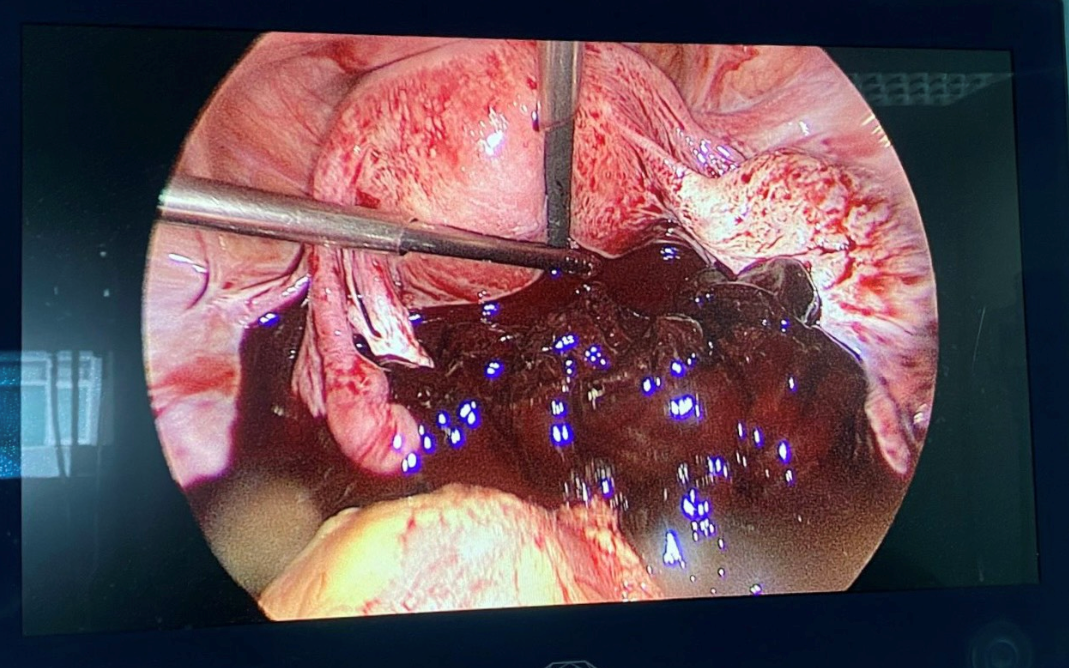

Phẫu thuật nội soi cắt khối “Thai ngoài tử cung vỡ” thực hiện ở bệnh viện đa khoa tỉnh Quảng Trị.